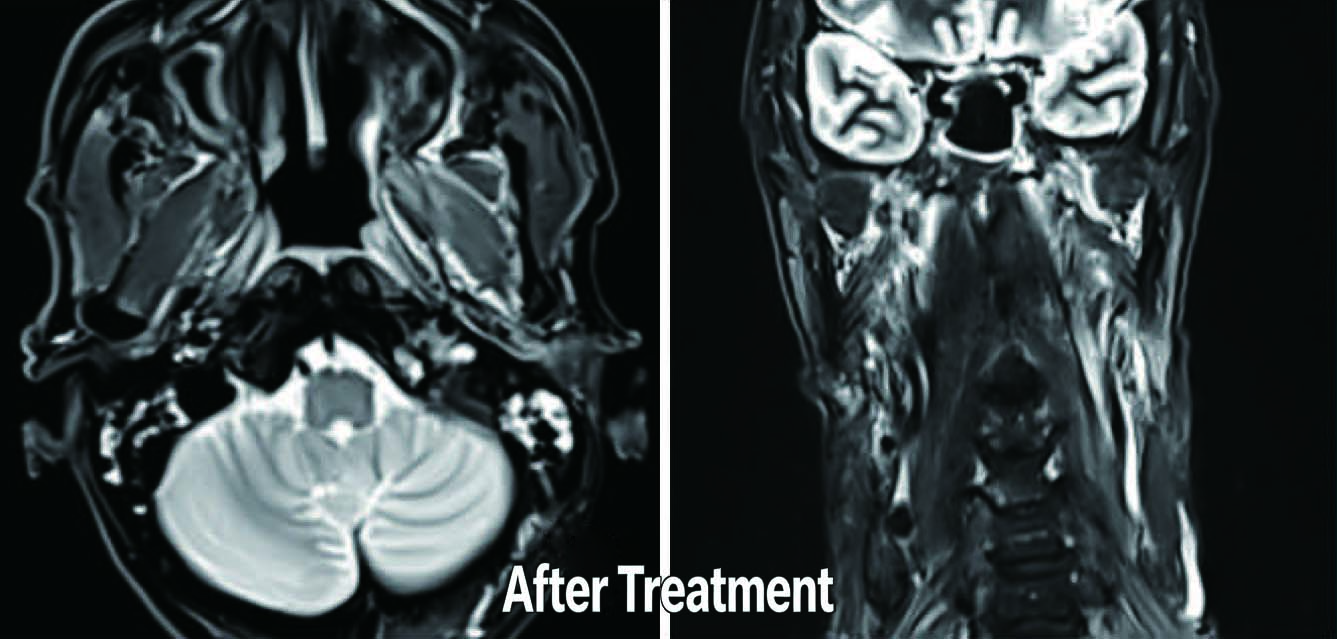

Patient: Male, 67 years old

Diagnosis: Bladder Cancer

Treatment Challenge: Tumor position varies with bladder filling, poor reproducibility.

Advantages of ETHOS Online Adaptive Treatment:

Utilizes iCBCT imaging before each treatment to capture the real-time position of the patient’s bladder and tumor. Allows for recontouring of the target area and redesigning of the treatment plan before each session, ensuring greater precision.

Illustrations include pre-treatment MR, target delineation during Ethos adaptive radiotherapy, and post-treatment MR.